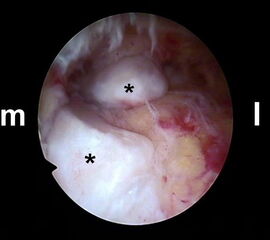

Abbildung Nr. 11-13

Das Os trigonum wird aus dem Weichteilgewebe gelöst und anschließend mit einer Fasszange entfernt. Bei größeren Knochenfragmenten muss ggf. das mediale Arthroskopieportal um wenige Millimeter verlängert werden, um die Extraktion zu ermöglichen. Nach Resektion des Os trigonum ist die posteriore Facette des Subtalargelenks erkennbar (rechte Seite, PF=posteriore Facette, FHL=Flexor hallucis longus-Sehne, T = Talus, K = Kalkaneus, *=Os trigonum).